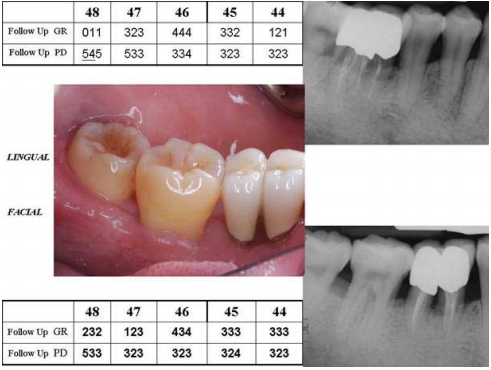

71.陳小姐34歲經牙周全口治療後,一年後進入支持性牙周治療,依下圖所示有關右下後牙區的敘述,下列何者錯誤?

(GR:gingival recession,PD:probing depth,數字下畫線代表探測流血) (A)#48舌側仍然有殘餘的牙周囊袋,故其回診不要超過3個月 (B)#46所做的牙根分離術(root separation),一般若失敗而拔牙其原因大多不是牙周病所引起 (C)#48舌側有殘餘的牙周囊袋又有牙周探測流血,此時可在做完預防性維持回診(preventive maintenance appointment)後1至2星期再行決定是否重新對陳小姐做牙周治療 (D)#46回診時仍然需要做牙齦下抗菌藥物的沖洗